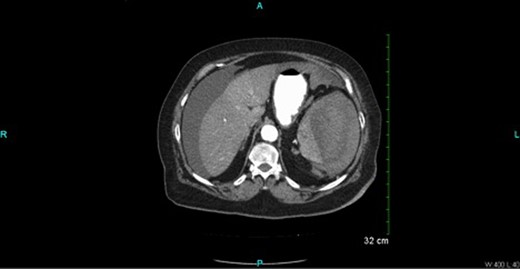

CT scan (Figs 2 and 3) revealed a large hematoma at the lateral margin of the spleen that displaced the spleen medially and compresses its lateral margin. A moderate amount of relatively low attenuation fluid also tracked into the right paracolic gutter and perihepatic space. There also appeared to be a 3.5 × 2.5 cm broad-based mass along the wall of the right colon. The CT scan of the chest also demonstrated a pulmonary embolus in a subsegmental artery of the right upper lobe. Given these findings, the patient was aggressively resuscitated with packed red blood cells and taken emergently to the operating theatre.

Oral and intravenous contrast-enhanced CT of the abdomen demonstrating air within the colonic lumen and a large haematoma at the lateral margin of the spleen that displaced the spleen medially, compressing its lateral margin. A moderate amount of relatively low attenuation fluid is also seen tracking into the right paracolic gutter and perihepatic space.